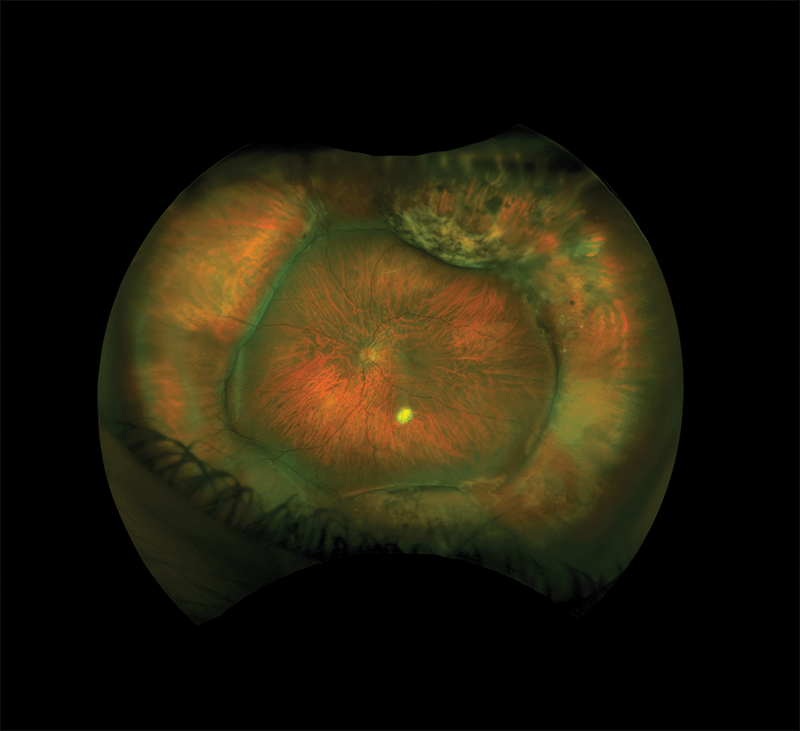

Although he had related a normal history, I knew there was more to the story when I observed the retinal imaging that the technician had acquired. From the optomap image (Figure), taken with a Daytona Plus (Optos), it was clear that this patient had previously undergone retinal detachment repair surgery in his left eye.

Upon further questioning, the patient confirmed that he had experienced a retinal detachment and had had surgery to repair it many years earlier. He also disclosed that he had undergone LASIK several years before the retinal detachment occurred and had perfect vision in both eyes until a scleral buckle repair of the retinal detachment created monovision for him due to the resulting myopic refraction.

When clinically examining a patient who has had a scleral buckle or band inserted, we never get to see the whole retina at once. Ultra-widefield optomap imaging, capturing up to a 200° field of view, can provide a unique opportunity to see the forest and not just the trees, and thereby to gain a new perspective on treating patients such as this one.